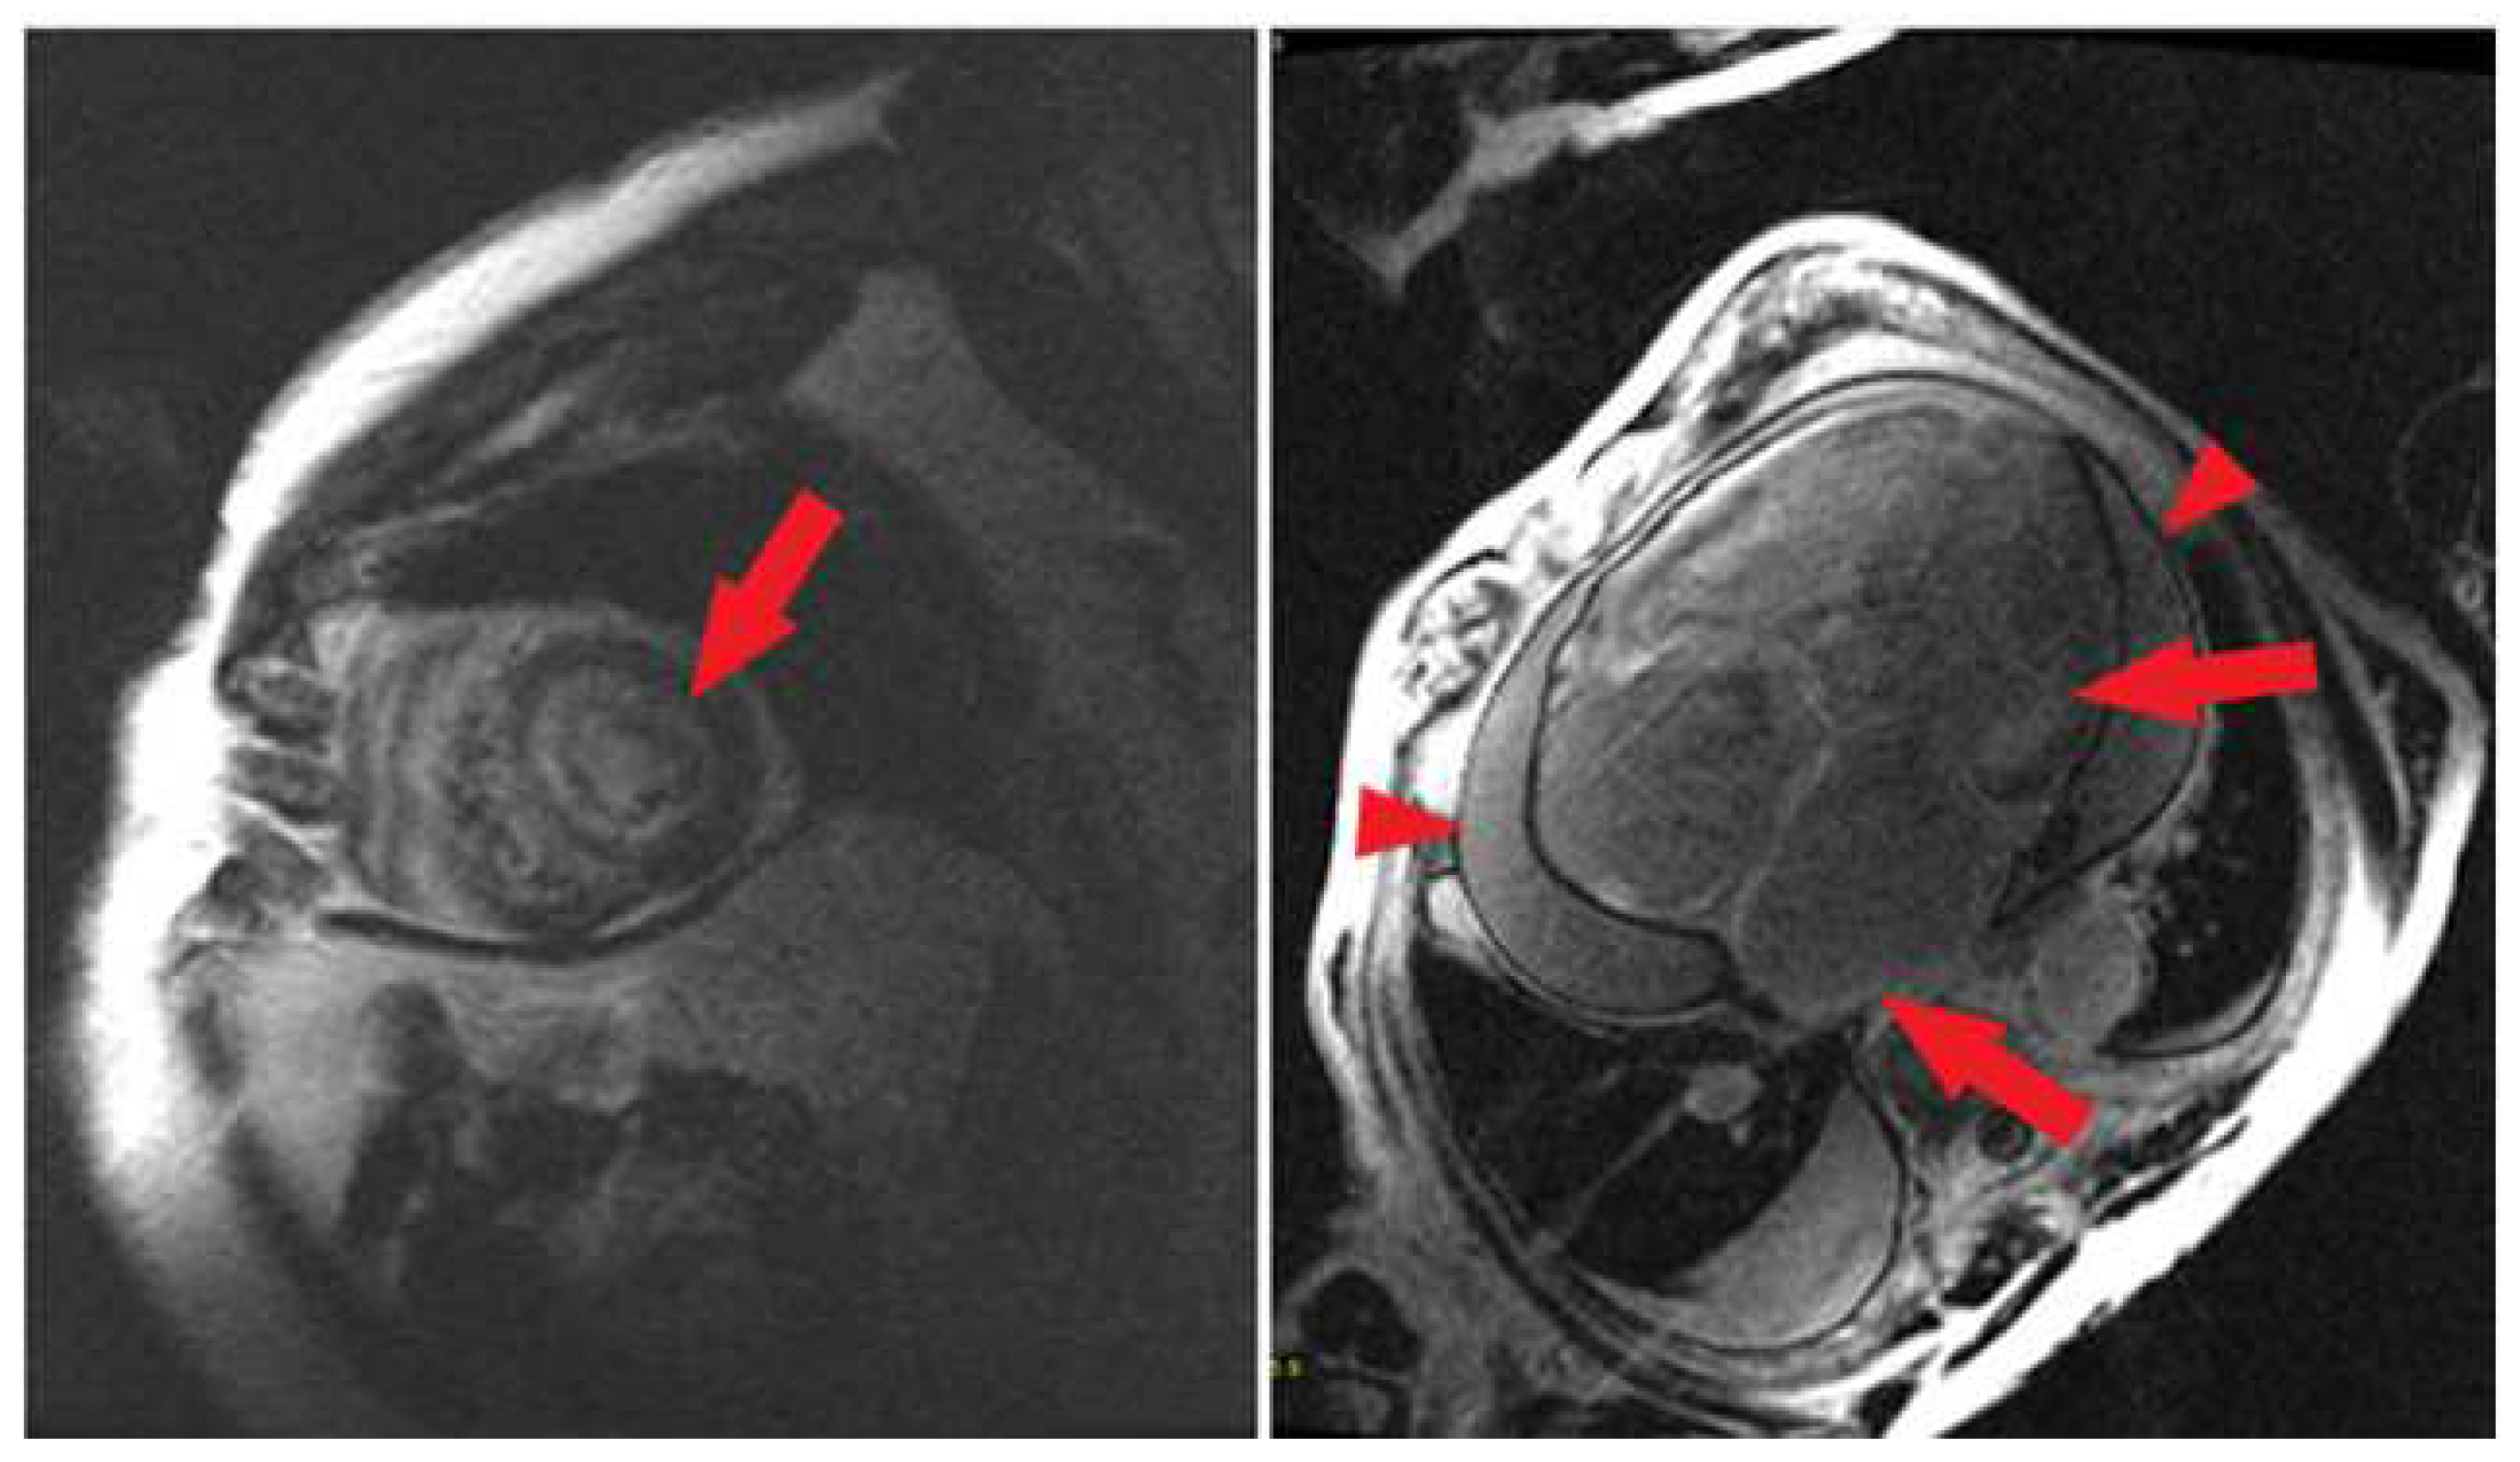

3.2. 3D Software Analysis

4.1. CMR Overview

4.2. Ventricular LGE

4.3. Atrial Amyloidosis

4.6. Ventricular Corridors and Scar Analysis